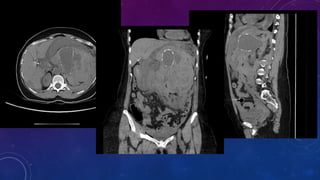

LEFT ADRENAL CALCIFICATION LIKELY FROM OLD TRAUMA

PRE RENAL TRANSPLANT EVALUATION.

WHAT ARE THE

Active extravasation from the

left gastric artery which was

successfully treated with coil

embolization.